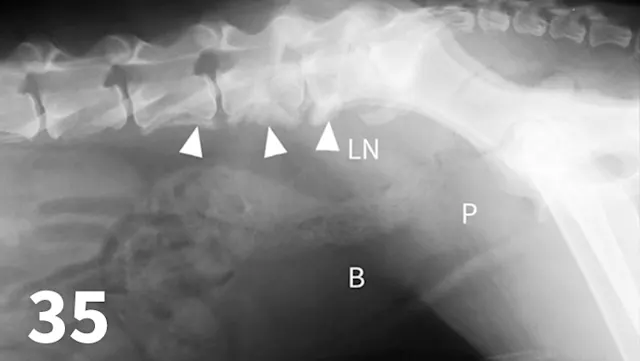

Survey radiography can be used to evaluate the size, shape, and opacity of the prostate gland (Figures 31 and 32). Ultrasonography has the advantage of providing tissue-architecture information. Prostatic abscesses, internal cysts, and paraprostatic cysts are readily visualized on ultrasonography. Ultrasonography can also aid in diagnosing benign hyperplasia (homogenous echotexture with intact capsule) and prostatic neoplasia (heterogenous with course echotexture and irregular margins) (Figure 33) and with identifying any potential source of excess androgen production (eg, adrenal glands, retained testes) in cases of suspected squamous metaplasia of the prostate gland. Mineralization of the prostate in a neutered dog is suggestive of neoplasia and can be detected by both survey radiography and ultrasonography. Sublumbar lymph nodes can also be evaluated by ultrasonography, whereas radiography is best for evaluating the adjacent lumbar spine (Figures 34 and 35).

The prostate gland (arrows) in this intact male dog is enlarged but normal in shape with smooth margins and soft tissue opacity. Although this is consistent with benign prostatic hypertrophy, ultrasound would be useful to further define tissue architecture.